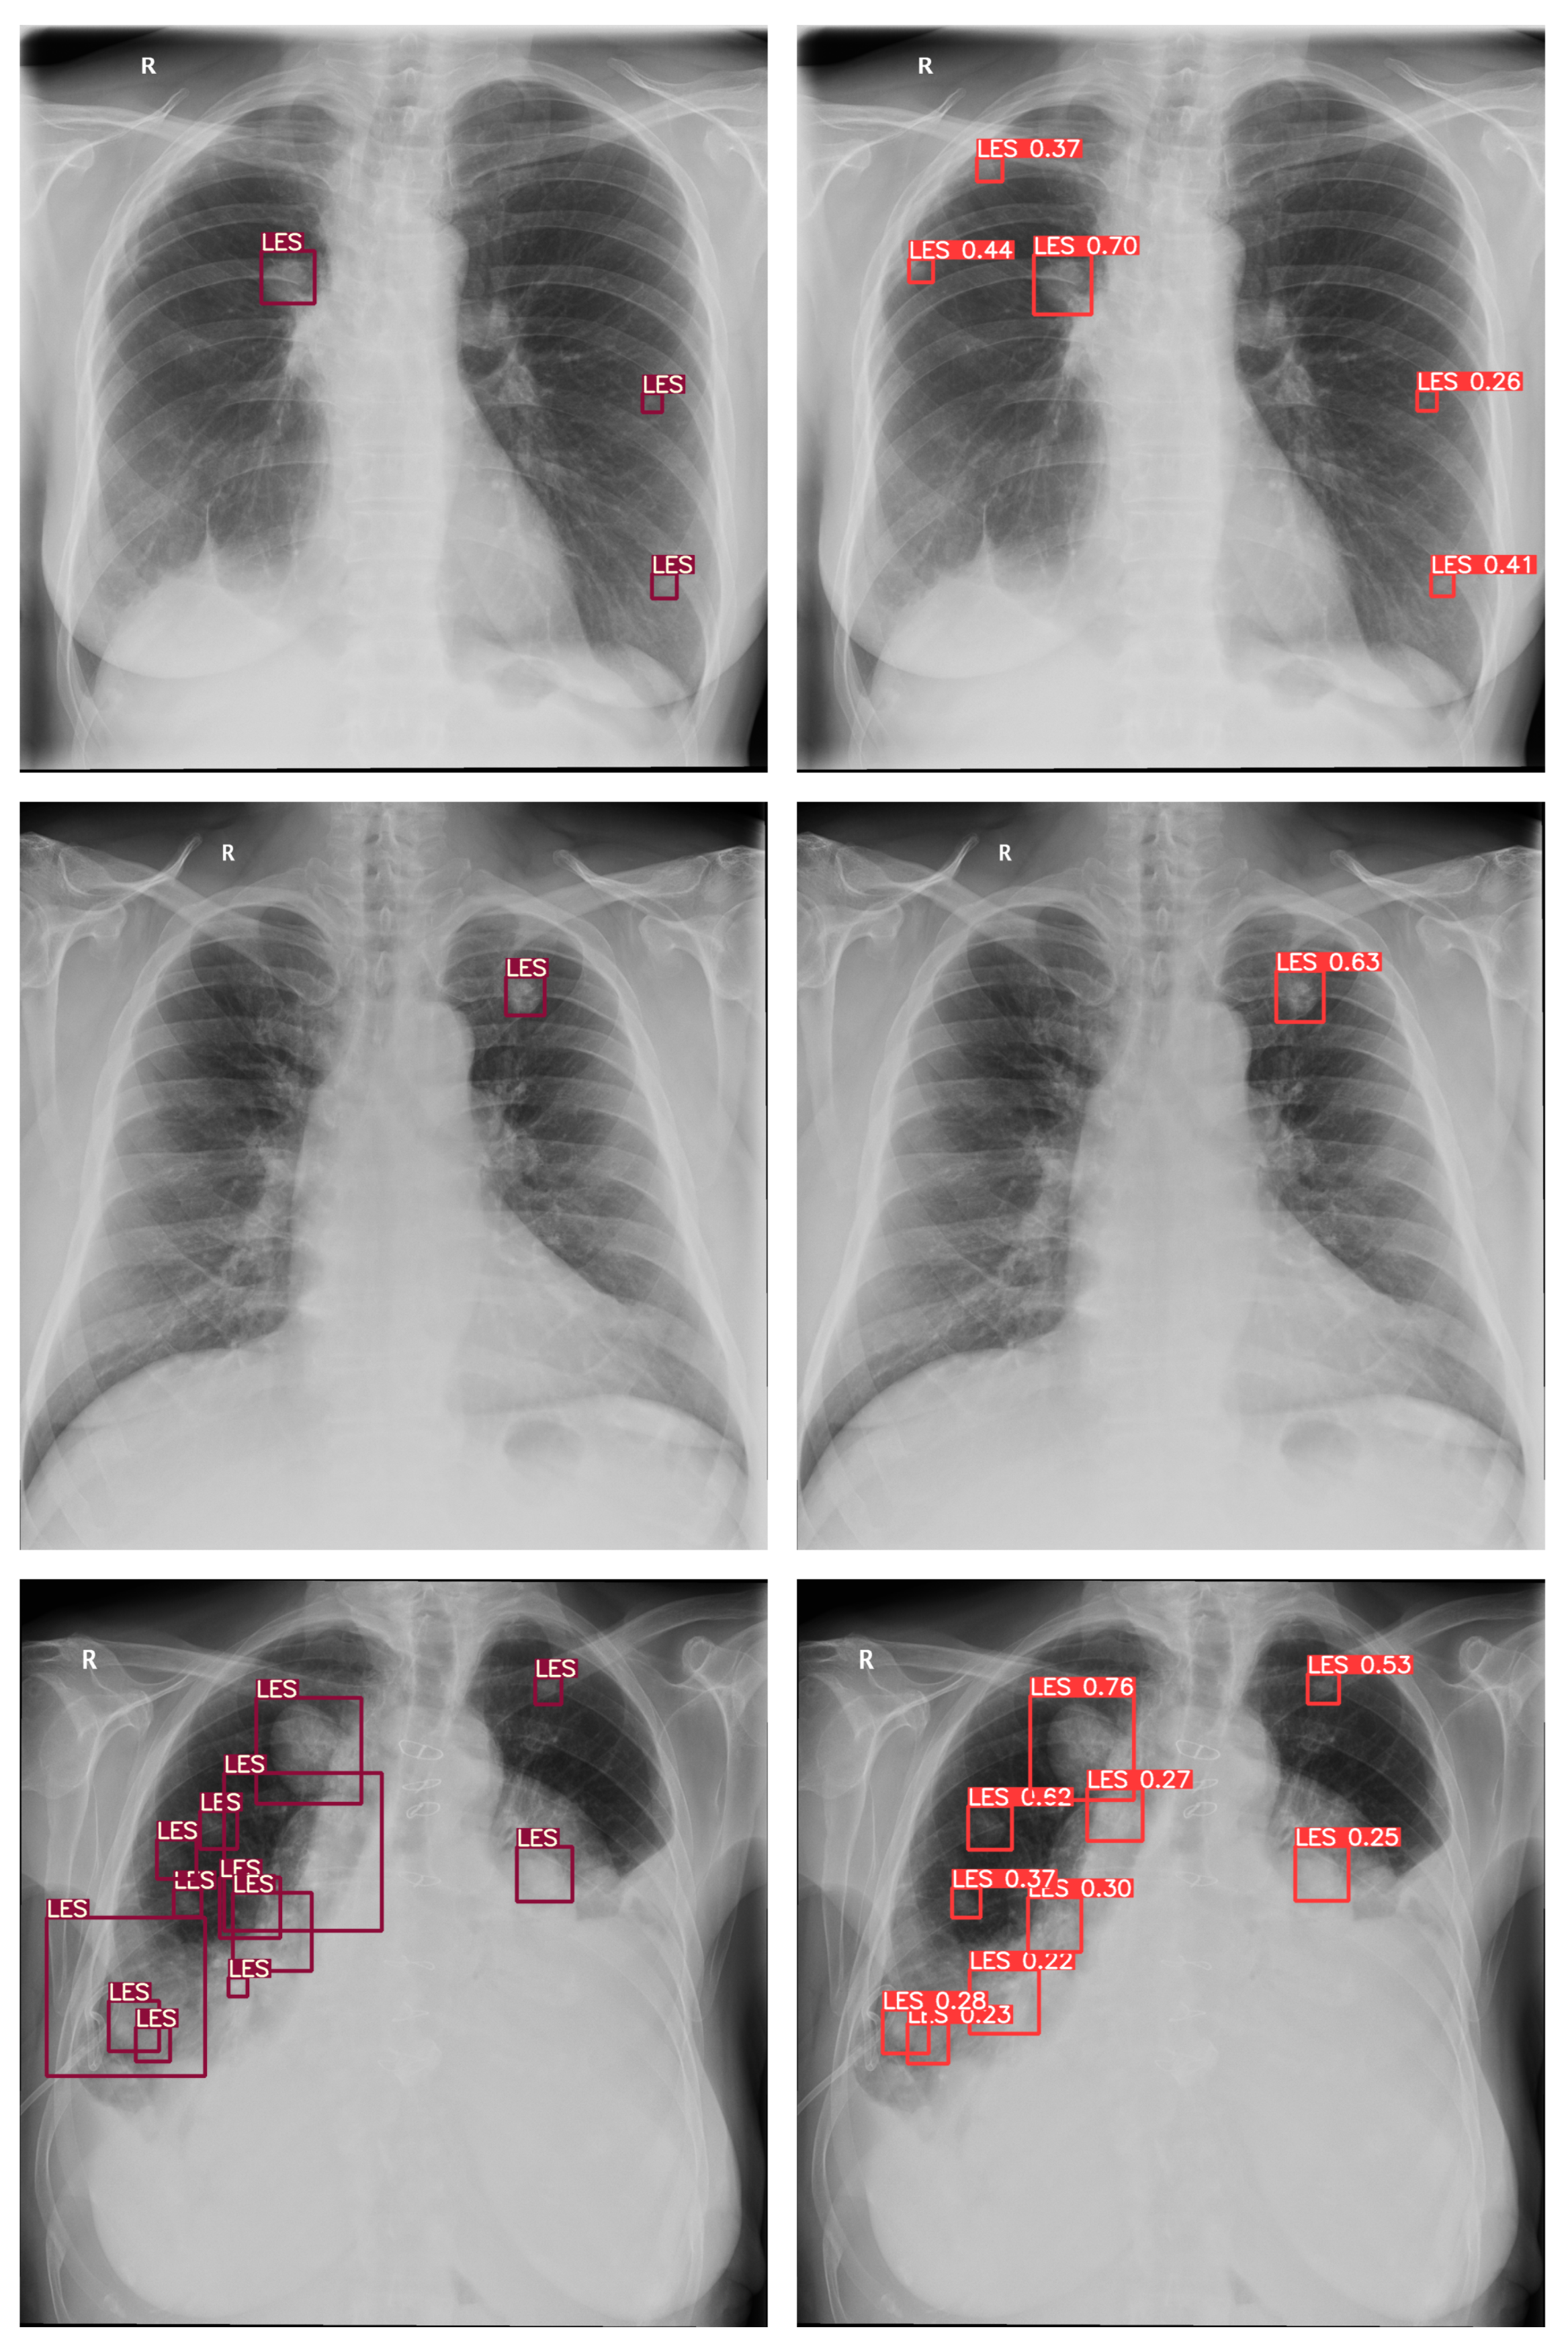

3.1.2. Model Architecture

3.5. Statistical Analysis

4. Results